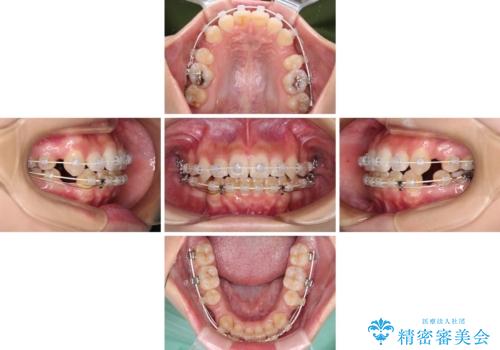

デコボコと八重歯の目立つ前歯 ワイヤー装置による抜歯矯正

- 上下前歯のデコボコと八重歯を気にして来院された患者様です。

叢生を解消する際に出っ歯とならないようにするために、上下左右の小臼歯計4本を抜歯することとしました。

奥歯の咬み合わせが理想的であり、歯の移動に時間のかかる出っ歯でもなかったため、2年程度で治療を終えることを目標としましたが、無事に予定通りの2年間で終えることができました。